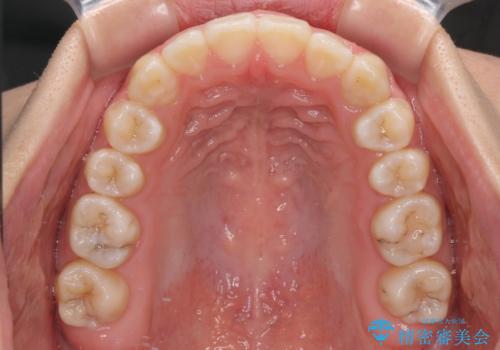

上顎骨を拡大することで、八重歯やデコボコを歯列に収めることができ、下顎の歯が外に位置していた奥歯の咬み合わせも改善することができました。

スペースも短期間に獲得できるため、1年程度で治療を終えることができました。